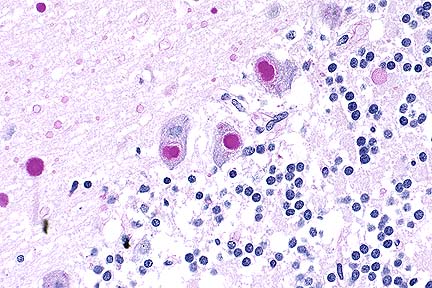

Numerous PAS-positive neuronal and glial inclusions in the cerebellum of a Maine Coon cat with tremors and seizure-like activity. (PAS, 100X, 65K)

Higher magnification of the field above, showing cytoplasmic inclusions within several Purkinje cells, as well as inclusions in unidentified cells in the molecular layer. (HE, 400X, 48K)

Contributor's Diagnosis and Comments: Cytoplasmic polyglucosan inclusions (Lafora bodies) within neuronal perikarya and processes, most numerous in Purkinje cells.

In sections of brain, there are few to many basophilic to amphophilic inclusions that occur within the cytoplasm of nerve cell bodies, neuronal processes, and scattered in the neuropil. These inclusions are usually round, range in size from 2 to 10 um diameter, and occasionally have a pale center or a thin, striated halo. These Lafora-like bodies are most numerous in the cerebellar molecular layers and within Purkinje cells, but are observed in all examined sections of brain.

Lafora bodies consist of complex polymers of glycoprotein, sometimes designated "polyglucosan bodies", and can occur within neuronal cell bodies or processes of the brain, spinal cord, or retinal ganglia. The round to globular basophilic cytoplasmic inclusions stain positively with PAS, alcian blue, and methenamine silver. In domestic animals, Lafora bodies have been observed most commonly in aging (at least 8 years of age) dogs and cats without apparent neurologic disease, but have also been described as incidental changes in some young animals. Lafora bodies have also been associated with a severe form of progressive myoclonus epilepsy in humans (juveniles) and dogs (young adult to middle-age), reflecting widespread intra-neuronal storage of these polyglucosans ("Lafora disease" or "neuronal glycoproteinosis"). The absence of other lesions to account for the observed neurologic signs incriminates the Lafora bodies as playing a role in the reported neurologic signs in this cat. In dogs with associated neurologic disease, the deposits are most commonly observed in Purkinje cells, similar to the distribution noted in this cat. In children with Lafora disease, other sites of polyglucosan deposition include skin and liver, and biopsies of these tissues have been used to help establish the diagnosis. Lafora bodies were not found in tissues from other than the CNS in this cat.

AFIP Diagnosis: Cerebellum, molecular and Purkinje cell layers: Polyglucosan bodies (Lafora bodies), neuronal and extracellular, diffuse, numerous, Maine-Coon, feline.

Conference Note: This case was also reviewed by AFIP's Department of Neuropathology. Lafora bodies are complex glycoprotein neuronal inclusions that can occur in the perikaryon, dendrites, or axons. They are PAS-positive and stain with alcian blue and methenamine silver. They can be found anywhere in the neuraxis and in retinal ganglion cells. Polyglucosan bodies have been associated with neurologic disease in humans, cats, dogs (Beagles, Basset Hounds, and Poodles), and a cockatiel. Lafora's disease in humans is a rare familial neurologic disorder of children. The disease is progressive and manifested by myoclonus. The characteristic histologic feature in the human disease is intraneuronal polyglucosan bodies, which occur predominantly in the substantia nigra and dentate nucleus. In dogs with neurologic disease attributed to the accumulation of intraneuronal polyglucosan bodies, the bodies are found predominantly within Purkinje cells and in thalamic neurons. In animals, Lafora bodies are frequently seen in the absence of neurologic disease. In these cases, the Lafora bodies can be found in any area of the brain and in the spinal cord.